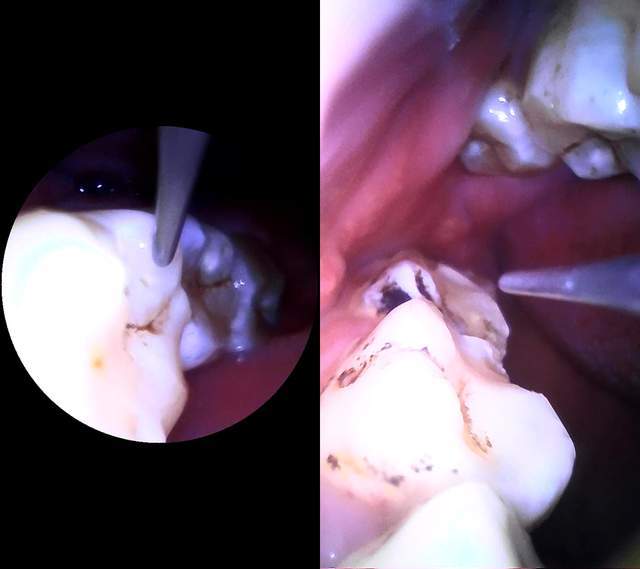

当本人一切准备就绪,打开了APP,把素诺智能可视超声波洁牙仪T11Pro探入口腔的那一刻,专业聚光LED灯一照亮整个口腔,APP上实时显示口腔内部环境,感觉是打开了一个新世界,真有点不可思议。

本人自认为一直以来早晚两次认真刷牙,没想到在T11Pro的500W高精内窥镜镜头之下,牙齿的顽固牙渍、牙垢全都暴露无遗,无处躲藏。当你发现自己的牙齿并不洁白,你就有一种迫切需要清理干净的渴望。

简单试用了下,T11Pro的牙渍、牙垢清洁效果,令人满意。素诺智能可视超声波洁牙仪T11Pro采用高效超声波换能器,大功率换能器将电能最大程度转换为超声波动能,带来42kHz超频共振,每分钟200W次声波震频,通过工作尖传递,与牙齿接触共振,当开启强力模式,能瞬间安全击碎牙结石,放心清理牙齿污渍,清洁效果确实不虚,强力、高效且直观。

这种直观体现在素诺智能可视超声波洁牙仪T11Pro搭载了500W高精内窥镜,摄像头搭载微距处理技术,所以能够清楚看到口腔内部环境,另外因为配备了领先的无人机专用Wi-Fi芯片,通过芯片图像处理技术,把500W镜头图像高速Wi-Fi传图至手机,直接就可以实时观看,洁牙操作起来方便,很人性化。素诺APP提供了水平和广角镜头画面,支持实时拍照和视频,还可进行分屏,功能丰富强大。通过T11Pro的可视化超强清洁力,可以让每个人拥有健康、美白的牙齿,让口腔洁净肉眼可见,T11Pro展现了一款高科技口腔护理产品该有的样子。

在操作过程中,不管是清洁哪个部位的牙齿,都能"指哪打哪",素诺智能可视超声波洁牙仪T11Pro除了500W高精内窥镜,还内置了四轴陀螺仪,能实现机身转动,镜头不变,加上内置多重传感器,通过智能软件算法,可实现360°精准刷牙。还有,不得不说,纤细的清洁头很灵巧,在清洁齿沟、牙齿缝隙等位置,表现得灵活精准。